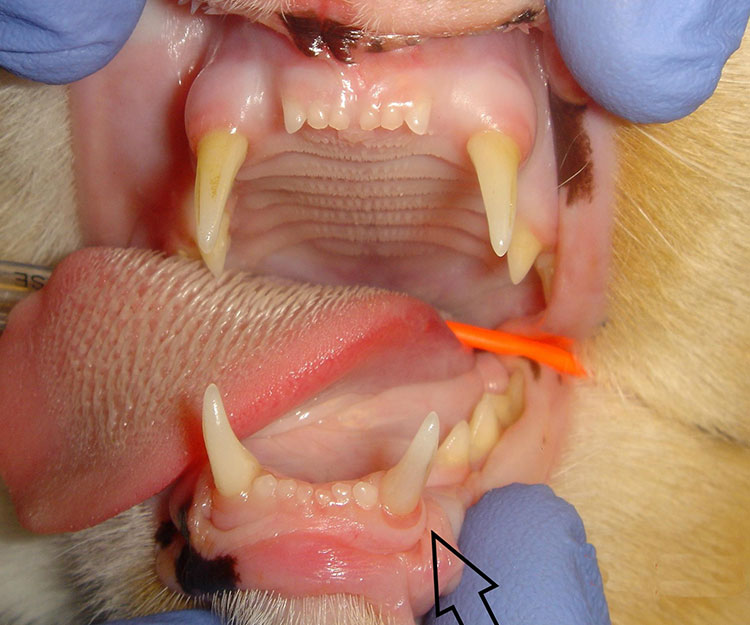

Surgery days are Tuesdays and Thursdays, with most procedures being dentals or soft-tissue surgeries.. As an assistant, I will help Dr. Stredel and the rest of the team with pre-surgical ECGs, bloodwork, patient induction, and care/monitoring during and after the procedure. Patient induction consists of placing a cephalic, forelimb IV catheter and sedating the patient over time. Through the course of about 15-20 minutes while the surgical suite is prepped, the patient will be injected with propofol, the initial sedative, and Convenia, a general antibiotic used to prevent infection during surgery. Once the patient is sedated and all of the equipment is prepped in surgery, the patient will be taken to the surgical suite, induced and maintained on gas isoflourane anesthesia, and undergo dental radiographs. Radiograph images are extremely important in veterinary dentistry, as they give the veterinarian a precise, inside look at the location, origin, and progression of various diseases. Throughout the procedure I will assist Dr. Stredel in monitoring and recording the patient’s blood pressure, heart and respiratory rate, & EtCO2 levels every 5 minutes to ensure the animal is in the proper anesthetic state. This photo above is of a 9 year-old schnauzer who was undergoing multiple tooth extractions due to progressive periodontal disease.